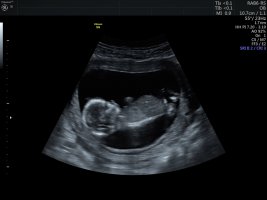

Benim bebeğime de bakar mısınız 12 hafta 3 günlük

• 4C3E9B76-EC32-4FDC-8BE0-366DA28A9F26.jpeg

4C3E9B76-EC32-4FDC-8BE0-366DA28A9F26.jpeg

209,5 KB · Görüntüleme: 457